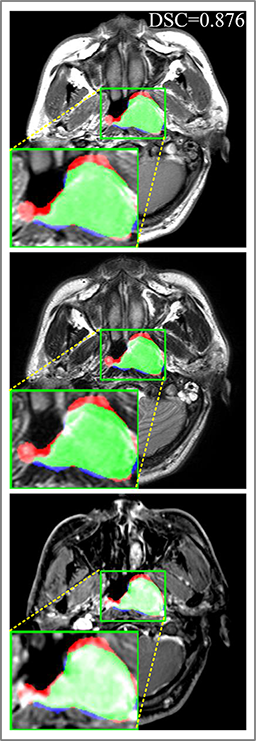

Refer to caption

(a) DSC=0.915

(b) DSC=0.870

(c) DSC=0.902

(d) DSC=0.898

Figure 7: Predicted results of proposed MMFNet in 2D images. There are corresponding T1, T2 and CET1 images from top to down. Boundaries created by radiologists are marked in red line, and the predicted boundaries are shown in blue line. The DSC𝐷𝑆𝐶DSC value is the dice similarity coefficient of this single slice.

Figure 9: Predicted results in one single slice image, there are corresponding T1, T2 and CET1 images from top to down. Green regions denote TP𝑇𝑃TP points, red and blue regions denote FP𝐹𝑃FP and FN𝐹𝑁FN point. (a) Ground truth. (b) Patch-based CNN (CET1). (c) Multi-modality patch-based CNN. (d) U-net (CET1). (e) 3D U-net (CET1). (f) Input-level fusion. (g) Merging encoders’ features. (h) MMFNet + multi-MLP + stdPool + self-transfer.

Comparison with ground truth. Some predicted results of MMFNet are shown in 2D images and 3D images in Figure 7 and Figure 8. As shown in these figures, although the shape and size of NPC are varied from each other, MMFNet can still accurately determine the regions of NPC and obtain the accurate contours of tumors. Through analyzing 2D images in figure 7, MMFNet has a capacity to fuse multi-modality MRI to reduce the confusion brought by intensity’ similarity between nearby tissues and NPC. The values of meanDSC𝑚𝑒𝑎𝑛𝐷𝑆𝐶meanDSC, meanASD𝑚𝑒𝑎𝑛𝐴𝑆𝐷meanASD and meanHD𝑚𝑒𝑎𝑛𝐻𝐷meanHD of MMFNet are shown in Table 1. MMFNet can reach the best results with DSC=72.38%,meanASD=2.07mmformulae-sequence𝐷𝑆𝐶percent72.38𝑚𝑒𝑎𝑛𝐴𝑆𝐷2.07𝑚𝑚DSC=72.38\%,meanASD=2.07mm, and meanHD=18.31mm𝑚𝑒𝑎𝑛𝐻𝐷18.31𝑚𝑚meanHD=18.31mm.

Comparison with related works. Table 1 reports the values of meanDSC𝑚𝑒𝑎𝑛𝐷𝑆𝐶meanDSC, meanASD𝑚𝑒𝑎𝑛𝐴𝑆𝐷meanASD and meanHD𝑚𝑒𝑎𝑛𝐻𝐷meanHD for different methods. Predicted masks of different methods are illustrated in Figure 9 and Figure 10, which respectively present results in 2D and 3D images. Through comprehensively analyzing these results, the proposed MMFNet actually have the following properties: